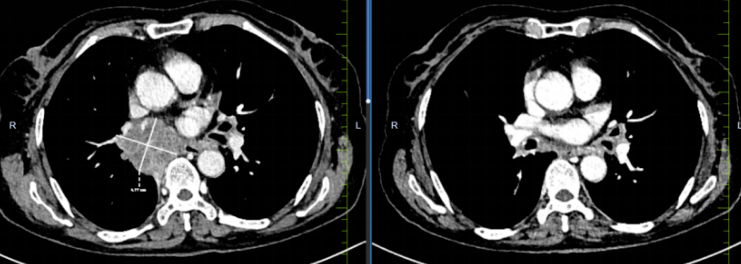

治疗中,团队严格遵循循证医学与国内最新指南,选用低毒高效化疗药物联合PD-L1抑制剂,既保证肿瘤杀伤效力,又最大程度降低骨髓抑制、胃肠道反应等老年患者不耐受风险。经6周期规范治疗,患者复查胸部CT显示肺部原发病灶缩小超80%,纵隔转移淋巴结明显消退,咳嗽、胸闷症状消失,体能状态从治疗前卧床不起恢复至可自主活动,达到该年龄段晚期小细胞肺癌患者的理想治疗反应。